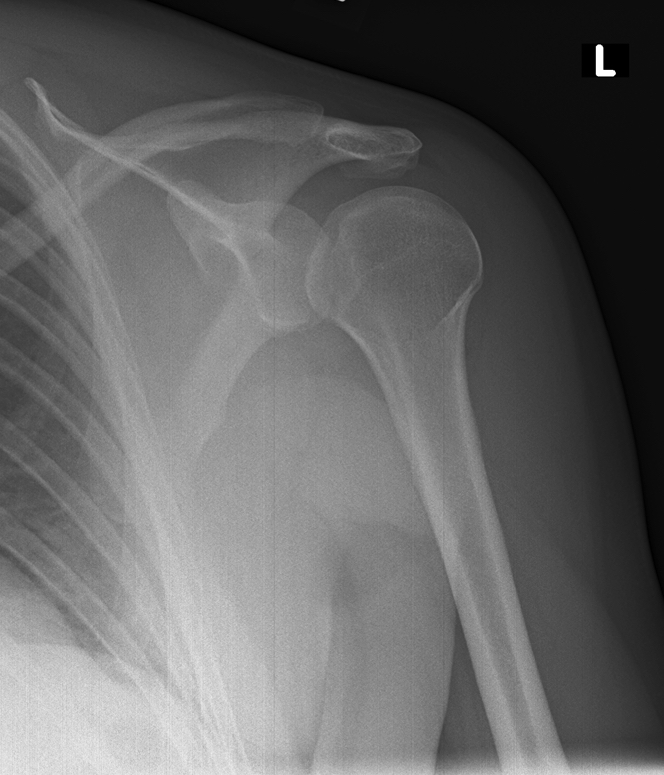

fall on outstretched hand

diagnosis?

posterior humeral dislocation

light bulb sign - fixed in internal rotation so humeral head looks more round (like light bulb)